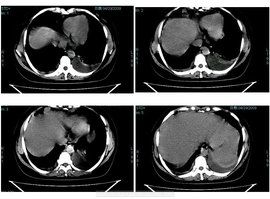

(六)脾臟腫瘤與脾囊腫

脾臟惡性腫瘤原發性者少見,轉移至脾臟的惡性腫瘤也罕見,原發癌灶多位於消化道。脾臟囊腫罕見,分真性和假性囊腫。真性囊腫分為表皮囊腫、內皮囊腫(如淋巴管囊腫)和寄生蟲性囊腫伯包蟲病人假性囊腫分為出血性、血清性或炎症性等。